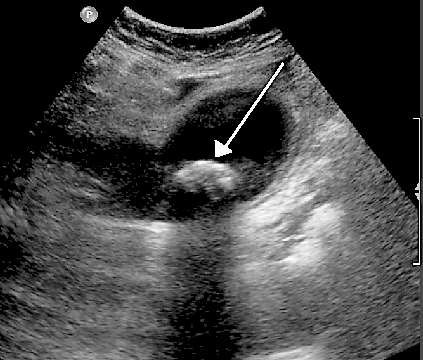

In many cases your symptoms, combined with tenderness in the upper right side of your tummy (abdomen), will alert the doctor that this is likely to be gallstones. However, tests are sometimes needed to rule out other conditions such as stomach ulcers, irritable bowel syndrome and tumours. An ultrasound scan (pictured) and blood tests are the most common investigations done. Other investigations including different types of scans such as an MRI may sometimes be required.